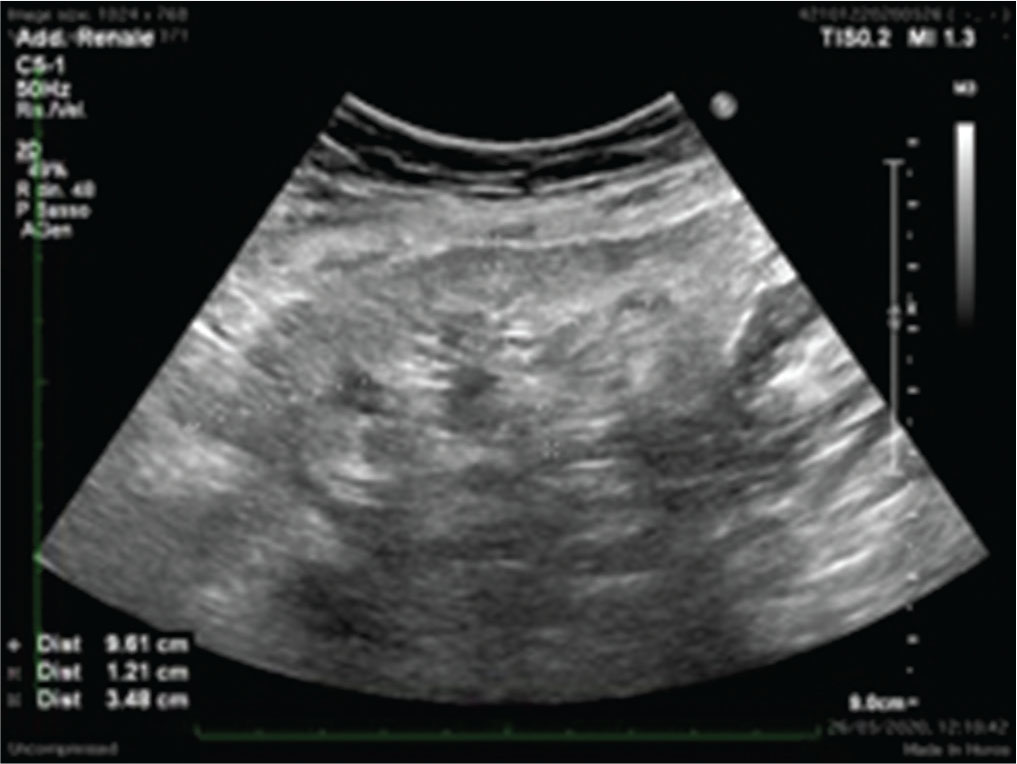

Lo studio Doppler del TR è altrettanto importante. Particolare attenzione andrà riservata alla valutazione del corretto flusso a carico delle arterie iliache, dell’anastomosi e della corretta vascolarizzazione all’interno del TR, con misurazione dei principali indici di flusso. Già in questa fase, le analisi color Doppler e, in particolare, il power Doppler possono essere molto sensibili nell’escludere la presenza di stenosi iliache/renali e di trombosi arteriose o venose, qualora ve ne sia il sospetto clinico (2).

Come si può ben apprezzare nella Figura 2, i vasi del TR sano sono certamente ben rappresentati, spesso addirittura in maniera migliore rispetto al rene nativo.

L’arteria renale normale è caratterizzata da una curva spettrale monofasica, con componenti diastoliche discrete. Andando più in periferia, la curva spettrale si caratterizza sempre per un tracciato a bassa resistenza, ma fortemente influenzato dalle condizioni generali del microcircolo arterioso del TR. Va effettuata un’accurata e globale valutazione degli indici di resistenza (IR), con valori normali che dovrebbero assestarsi sempre uniformemente sotto 0,8, campionando quante più zone possibili del TR.

(Personal image, Fondazione IRCCS Ca’ Granda Ospedale Maggiore Policlinico, Milano)